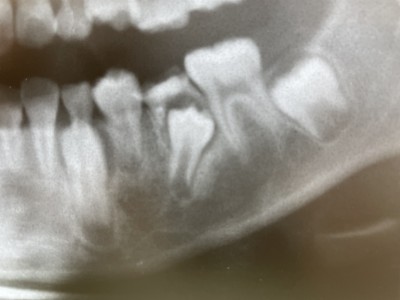

【親知らず】の活用法

2020.02.18 症例紹介